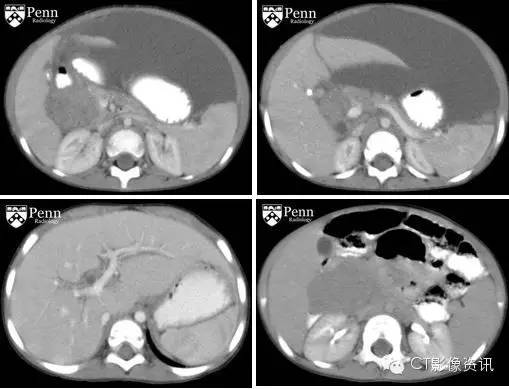

病史 女,2岁,无痛性黄疸。血清α-甲胎蛋白8500ng/mL

增强CT图像如下

影像学描述 腹部及盆腔增强扫描CT发现:胰头区域一个类圆形边界清晰的肿块。最大直径112.5px,肿块成分混杂,相对胰腺实质呈低密度改变。肿瘤位于胆总管远端,导致近端胆总管适度扩张(左下图)。肝脏未见转移。左侧腹膜后一枚实性肿大的淋巴结(右下图),提示转移。中等量的腹水。